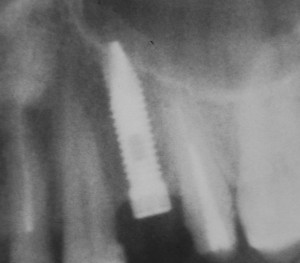

Рисунок 46, 47, 48. Стабилизация импланта при толщине костной ткани менее 3 мм: слева – установка импланта после синуслифтинга, в центре – заполнение субантрального пространства спейсером, справа – рентгенологический контроль.